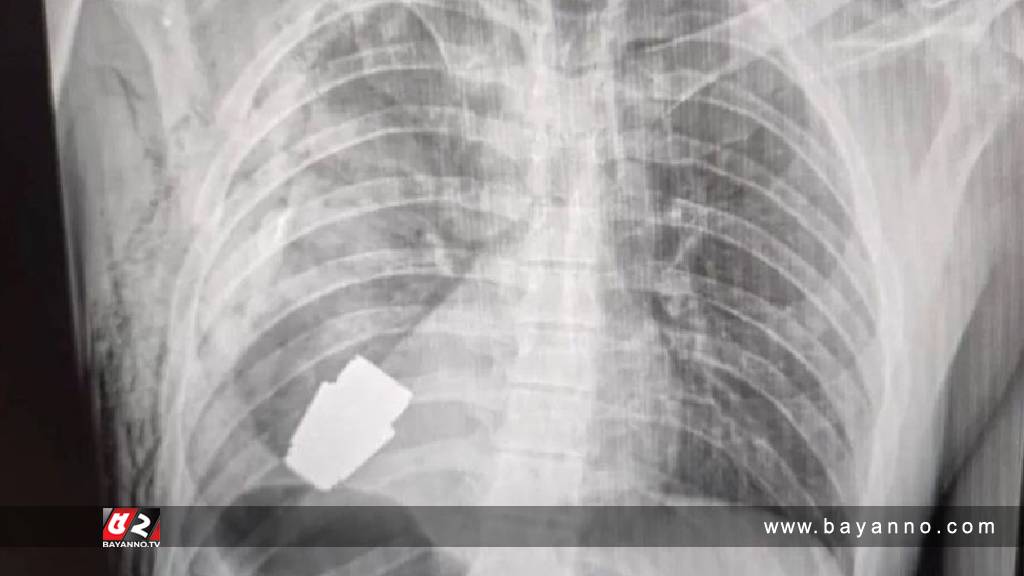

অপ্রতাশিতভাবে এক সেনা সদস্যের বুকের মধ্যে ঢুকে যায় একটি গ্রেনেড। এরপরই দেখা দেয় বিপত্তি। ওই সেনা সদস্যের একটি ছবি সামাজিক যোগাযোগ মাধ্যমে ভাইরাল হয়েছে। যেখানে এক্সরের একটি রিপোর্টে সেনা সদস্যের বুকের মধ্যে অবিস্ফোরিত গ্রেডেনের ছবি দেখা যাচ্ছে। দুজন সেনাবাহিনীর সহযোগিতায় ওই সেনা সদস্যের বুক থেকে গ্রেনেডটি অপসারণ করা হয়েছে। এখন তিনি কিছুটা সুস্থ। গ্রেনেডটি ৪ সেন্টিমিটার লম্বা। এটি লঞ্চারের মাধ্যমে নিক্ষেপ করা হয়। অপারেশন করার পর মেজর জেনারেল অ্যানড্রিল ভারবা বলেন, এ ধরনের ঘটনা খুবই বিরল। তবে কীভাবে বুকে গ্রেনেড ঢুকেছে সে সম্পর্কে বিস্তারিত কিছুই বলা হয়নি। বলা হয়েছে রুশ সেনাবাহিনীর বিরুদ্ধে অভিযান পরিচালনা করতে গিয়ে এ ধরনের ঘটনা ঘটে। কোথায় অভিযান পরিচালনা করা হয়েছে সে সম্পর্কে বিস্তারিত কিছু বলা হয়নি। সামাজিক যোগাযোগ মাধ্যমে দেওয়া পোস্টে বলা হয়, ইলেকট্রোকোয়াগুলেশন পদ্ধতি ব্যবহার না করে সাধারণ পদ্ধতিতে গ্রেনেডটি অপসারণ করা হয়েছে। কারণ এধরনের গ্রেডেন যেকোনো সময় বিস্ফোরিত হওয়ার সম্ভাবনা থাকে।